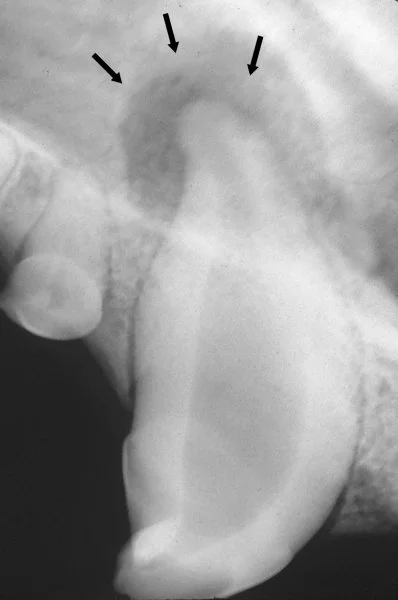

이 그림이 정말 좋은 예인데, 치석은 노란색이고, 자주색부분이 잇몸의 끝라인이에요. 즉 자주색라인보다 밑부분만이 육안적으로 보이는 치석이고, 위에 부분은 잇몸안에 있는 치석입니다.

마취가 된 후에는 구강상태를 평가하고, 치열, 치석 및 플라그에 대해 평가합니다. 치아 방사선을 촬영을 통한 치아 뿌리 및 주변 뼈들에 대한 상태를 볼 수도 있습니다. 만약에 치주질환이 매우 심하다면, 치아를 살리는 게 불가능할 수도 있는데, 이 경우 치아를 발치합니다. 이후에 스케일링이 시작되는데, 스케일링을 통해서 잇몸 라인의 위아래로 스케일리을 하게 됩니다. 잇몸 안쪽의 치석은 매우 심각한 잇몸 손실을 유발할 수 있기 때문에, 가장 중요하게 제거됩니다. 스케일링 이후에, 폴리싱을 통해, 아주 미세한 상처들을 마모하는데, 이런 상처들에 이차적인 플라그가 형성되기 쉽기 때문입니다. 그 외 플루오이드나, 항생제, 그리고 세정제등을 이용해서 치아의 민감도를 낮추고, 에나멜질을 강하게 하고, 세균을 컨트롤합니다. 그리고 미래의 플라그 축적을 감소시킵니다.